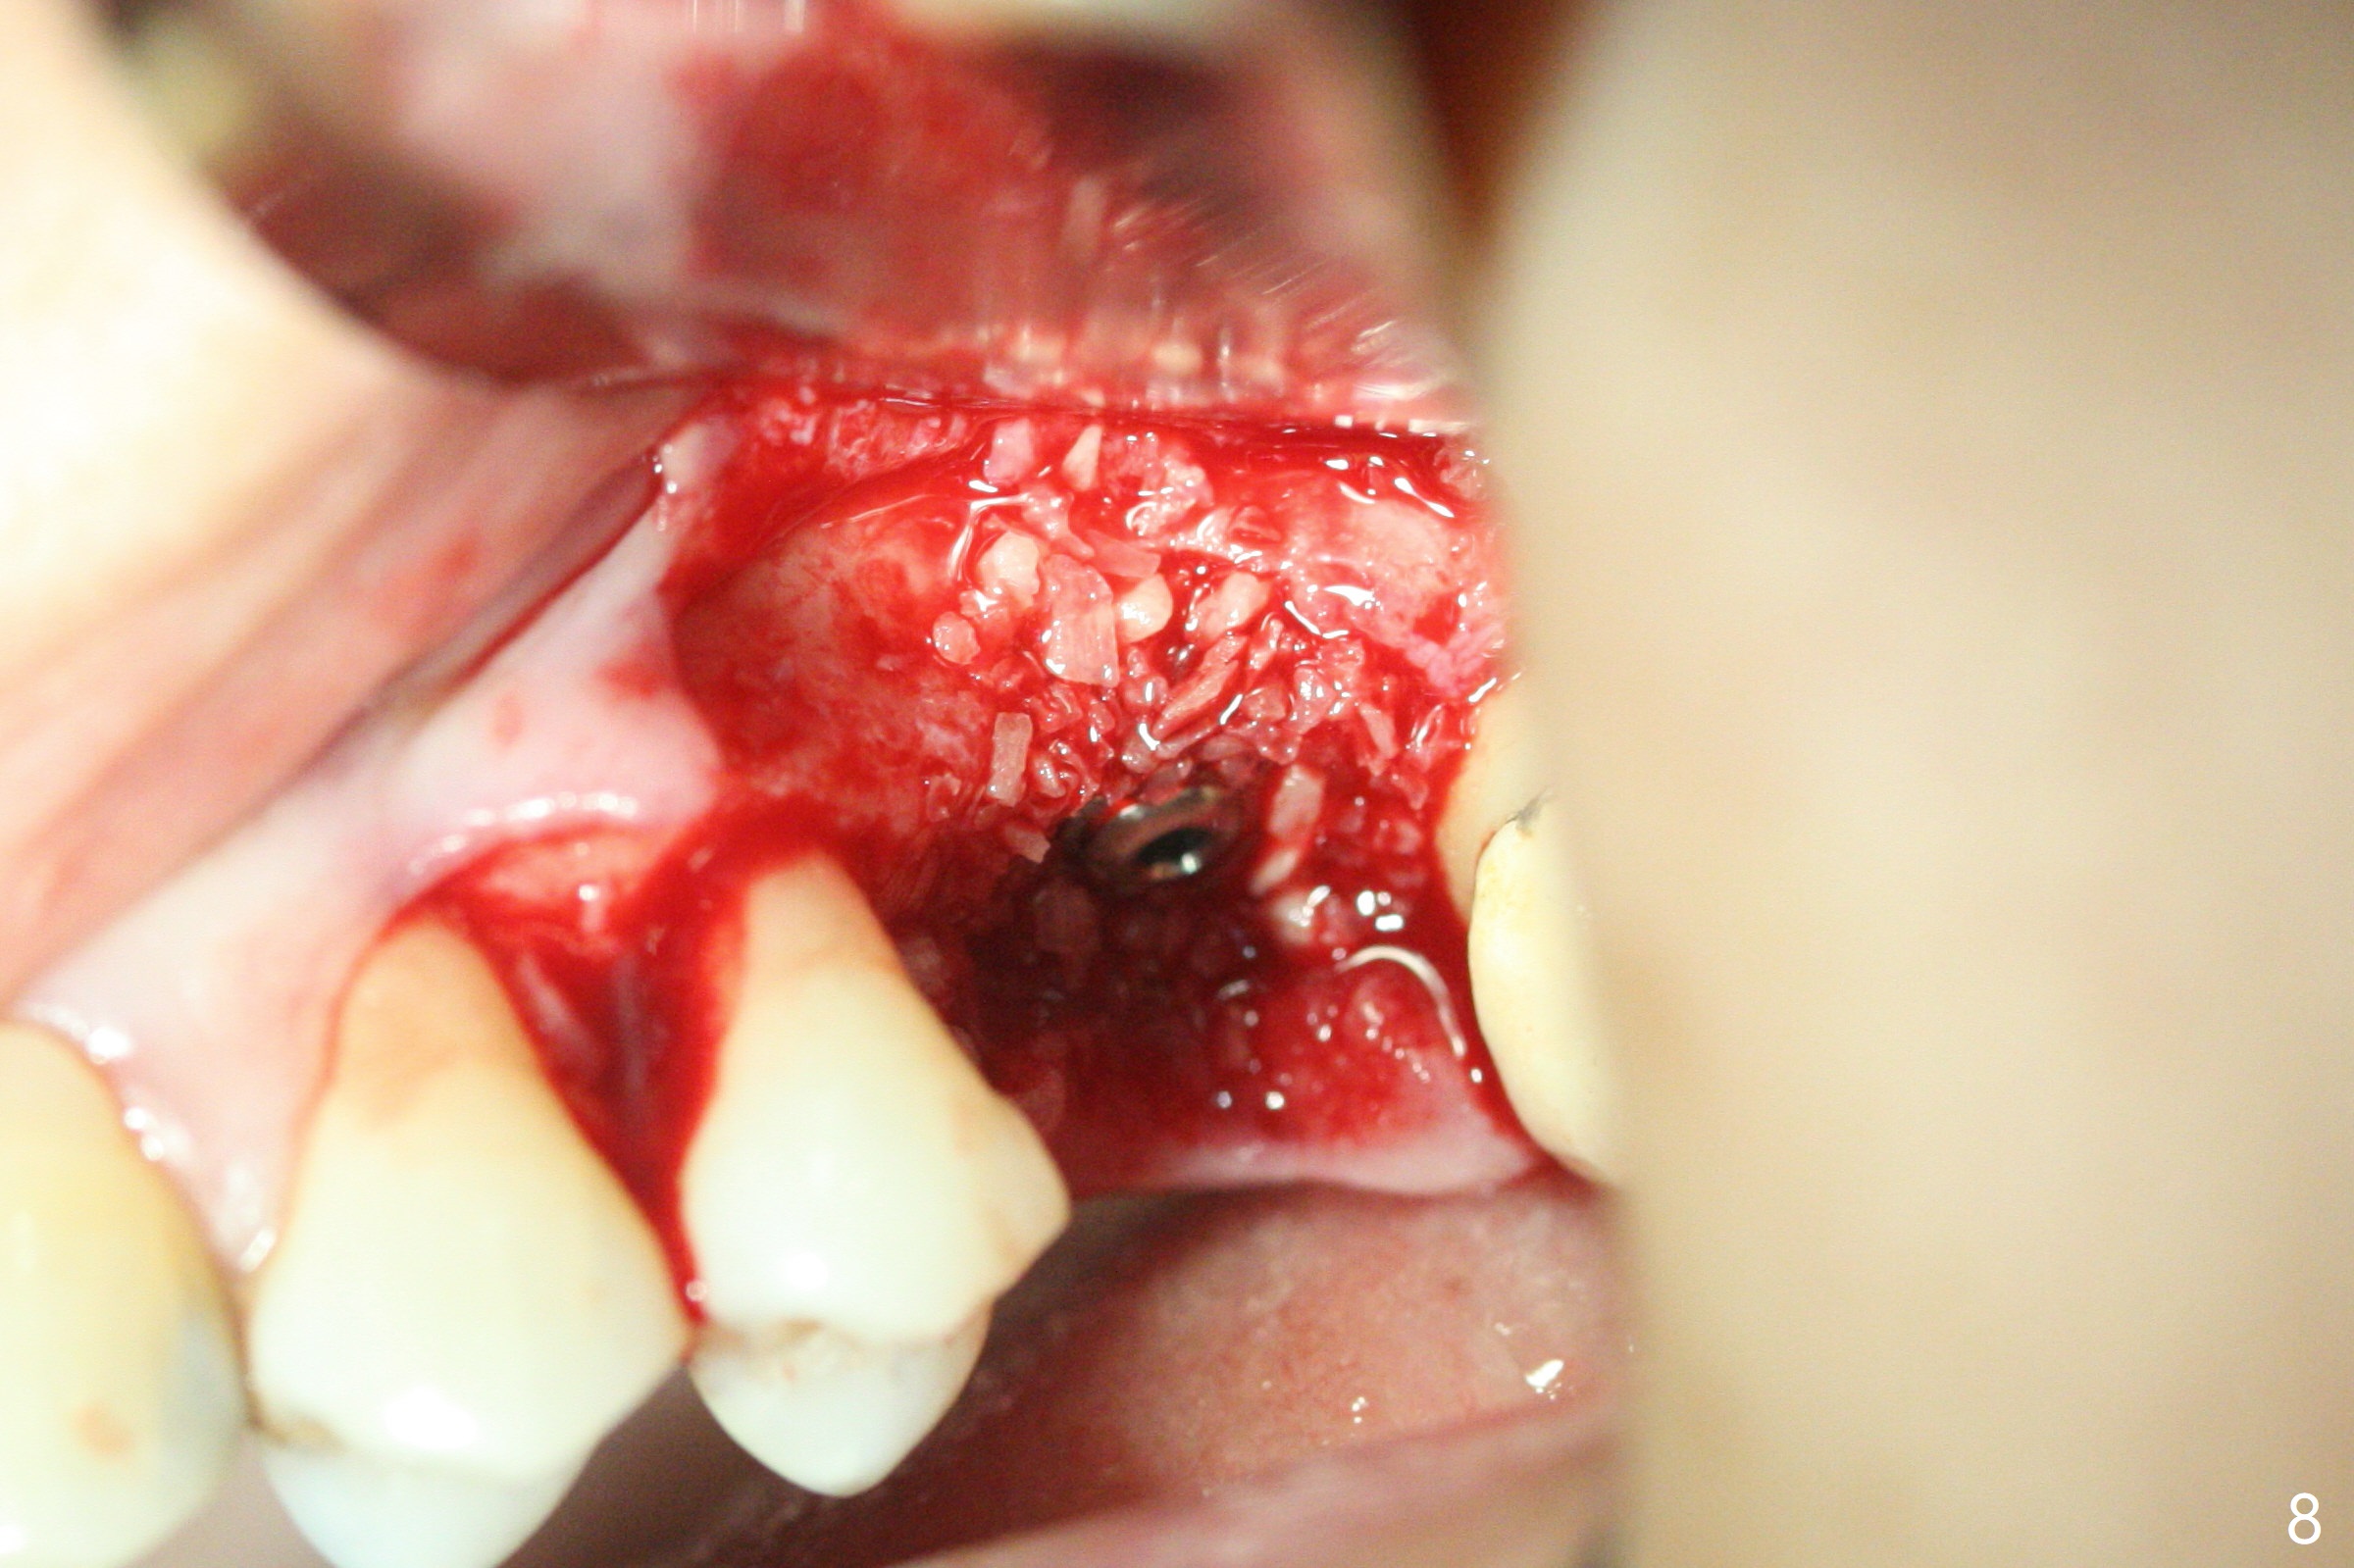

A 57-year-old woman complains of bad smell while use of water flosser between 11 and 21 months post cementation of implant crown at #14 (Fig.1,2). Bone loss is more obvious with CBCT (Fig.3,4), in spite of apparently normal gingiva around the implant after removal of the abutment and crown (Fig.5). In fact the buccal (B) gingiva is fragile with easy access to the underlying implant plateau. Following flap elevation, the bone loss is evident (Fig.6), but the implant plateau is slightly subcrestal (Fig.7 *). The exposed implant threads are covered with the 1st round of bone graft (Fig.8). After 2nd round of allograft (Fig.10-12) and collagen membrane, the flaps are approximated (Fig.9). The wound is covered by acrylic dressing. The latter is loose, but stays in place 1 week postop (Fig.13). Due to short neighboring teeth, the acrylic dressing is able to be removed with wiggling; it appears that the wound is healing (Fig.14). The dressing returns for another 2 weeks; some of the graft has been lost (Fig.15). The dressing does not return 7 weeks postop, since the wound is healing (Fig.16).